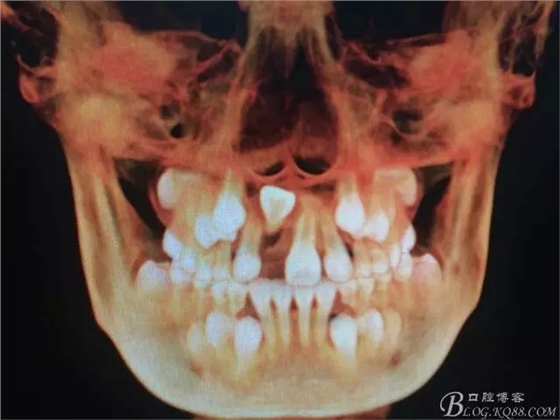

圖2.術(shù)前的CBCT的三維影像重建:多生牙的位置

圖3.右上11的三維影像位置。